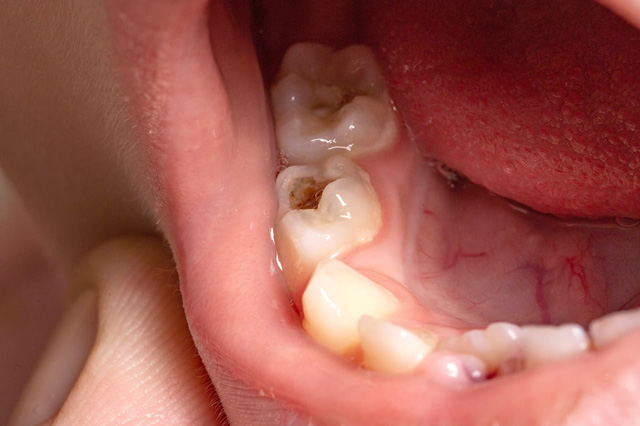

むし歯がエナメル質の内側にある象牙質まで達している状態です。むし歯の部分は黒く見えます。冷たいものや甘いものを飲食したときに、しみる・痛むなどの自覚症状が現れます。この段階から進行が早くなるため早期の治療が重要になります。

治療方法

むし歯の部分を削り取り、詰め物で補います。症状によっては局所麻酔を使用します。